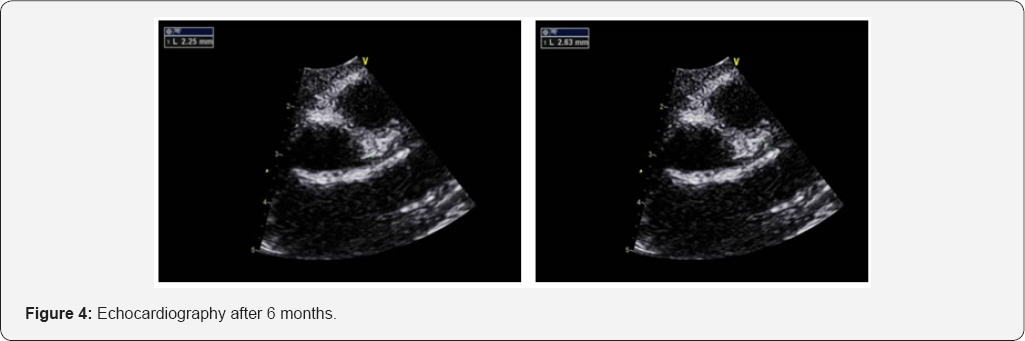

After 6 months the Echo showed mild ectasia along the course of both coronaries, LCA at the origin 2.9mm and LAD 2.2mm. Small aneurysmal formation measuring 2.8mm at the origin of RCA (Figure 4).